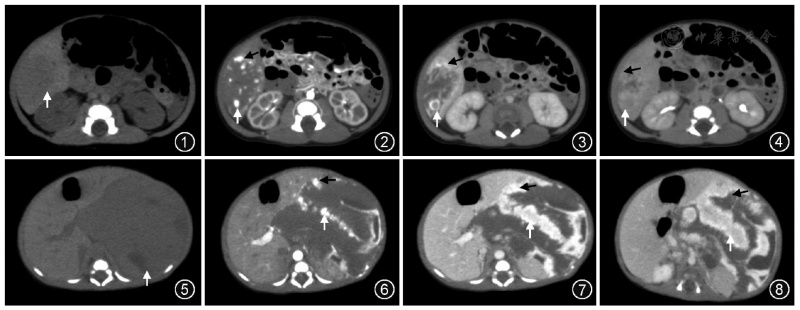

肝母细胞瘤是儿童最常见的肝脏恶性肿瘤,约占儿童肝脏恶性肿瘤的60%~70%,尽管早期常规治疗后无瘤生存率已接近70%,但复发后的治疗仍是医学界的一大难题——临床数据显示,复发后肝母细胞瘤患儿若伴随多脏器侵犯,5年生存率仅为40%~60%,救治难度呈几何倍数增加。小航的病情,正是这种极端凶险的情况:经过3次手术和8个周期的放化疗后,肿瘤再度复发,不仅盘踞肝脏形成直径约7.5cm的病灶,还迅速侵袭胰脏、胆道等重要脏器,形成了两大致命困境——肝脏肿瘤引发门静脉癌栓,而合并门静脉癌栓的患儿,不经积极治疗中位生存期仅2~3个月,即使接受综合治疗,中位生存期也仅10~16个月,同时癌栓还导致脾肿大,患儿血小板计数降至正常范围下限的60%;此外,肿瘤压迫胆道造成梗阻,患儿血清胆红素水平飙升至320μmol/L,远超正常上限(17.1μmol/L),随时可能引发肝衰竭。“这两个问题需同时解决,难度极高,相当于在生命禁区里走钢丝。”参与救治的医生坦言。

面对这一罕见病例,常规手术方案早已无法适用。多学科诊疗团队迅速联动北京京都儿童医院肝胆外科专家——该科室专家深耕儿童肝母细胞瘤、胰母细胞瘤等腹部实体肿瘤诊疗15余年,累计完成儿童复杂肝胆手术超1200例,其中复发难治性肝母细胞瘤手术300余例,手术成功率达92%以上,尤其擅长复发难治性肝脏肿瘤的综合救治与复杂术式的精准实施,双方展开8轮联合会诊,反复推演手术细节、评估风险。最终,联合团队大胆决定采用“离体肝切除+自体肝移植+胰十二指肠切除术”这一超复杂术式——要知道,离体肝切除联合自体肝移植被誉为肝胆外科“皇冠上的明珠”,集多种高难度技术于一身,临床数据显示,该术式用于恶性肿瘤治疗时,30天内死亡率约6.96%,主要并发症发生率达27.91%,而联合胰十二指肠切除后,手术复杂度更是呈指数级提升,术中血管吻合精度需控制在0.1毫米以内,对医生的技术精度、团队的协作能力,都是前所未有的考验,目前全球范围内此类联合手术仅成功实施1例。